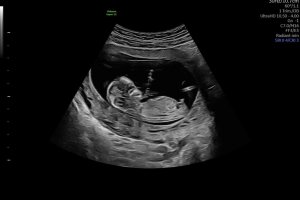

Åå, så kjedelig med dårlige bilder :/.. Jeg har dette også, men her ser man heller ikke stort. Jordmor sa ingenting om hva hun trodde eller noe som helst om kjønnet..Disse bildene var veldig dårlig til å være 14 uker. har du flere fra denne eller tidligere? burde være lett å se kjønn når man er så langt på vei. det på bilde nr 1 er ikke nub, det er en del av benet som har kommet med på bildet. Jeg tror det er jente da det ville vært veldig synlig i uke 14 om det var gutt. Ser og lang hvit strek på flere av bildene som samsvarer med jentenub.

trodde kanskje det var noe ) se hvor jeg har satt ring på bildet hihi

? Er 13+1 her